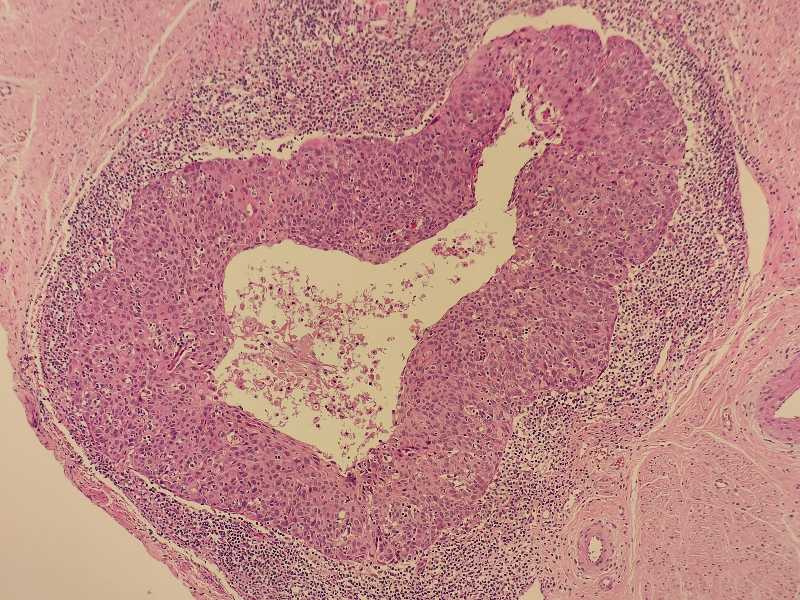

女40岁宫颈锥切组织浸润还是CIN累腺

女40岁宫颈锥切组织 浸润还是CIN累腺?

考虑:鳞癌